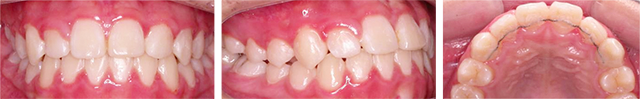

공간부족으로 인하여 치아가 제대로 나오는 못한 2급 부정교합 환자입니다. 고운미소에서 악궁을 넓혀주는 급속구개확장술 (RPE)를 적용하여 비발치 교정을 진행하였습니다.

급속구개확장술 (RPE) 장치로 빠르게 상악이 확장되었습니다. 넓어진 공간으로 치아가 이동이 되어 발치를 하지 않고 가지런하게 치아교정이 되었습니다.